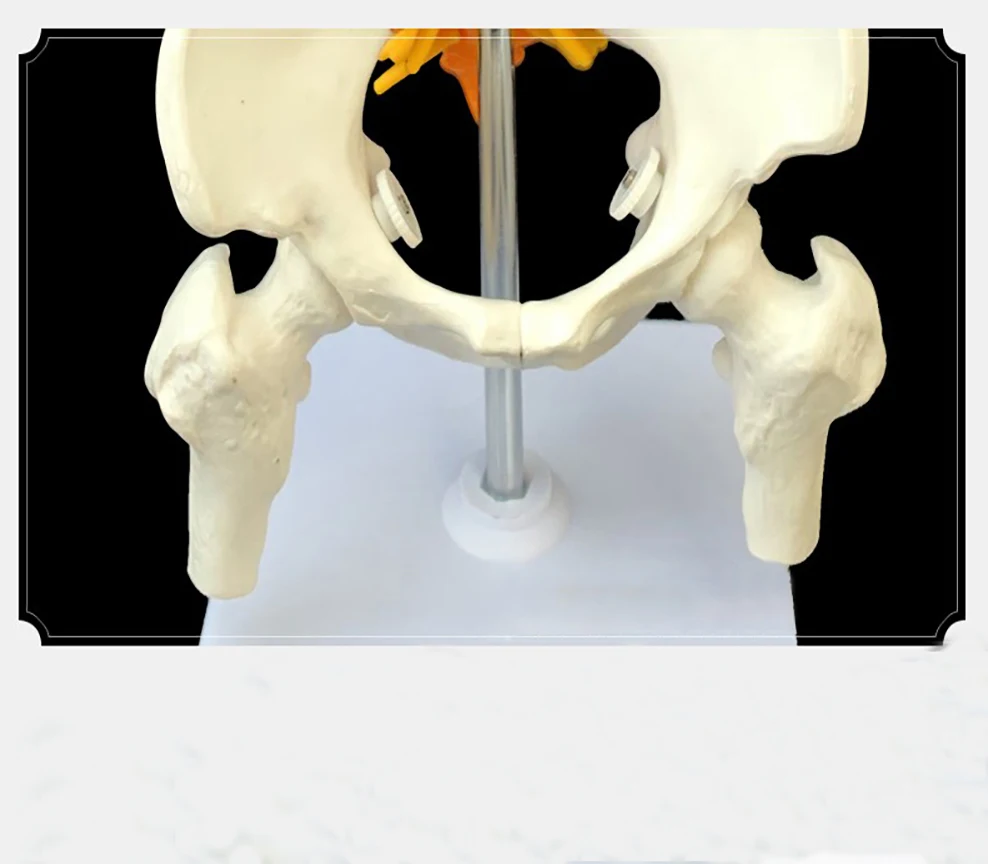

1: 1 human spine skeleton model adult orthopedic exercises with cervical lumbar discs color spine skeleton model High quality

aliexpress.com